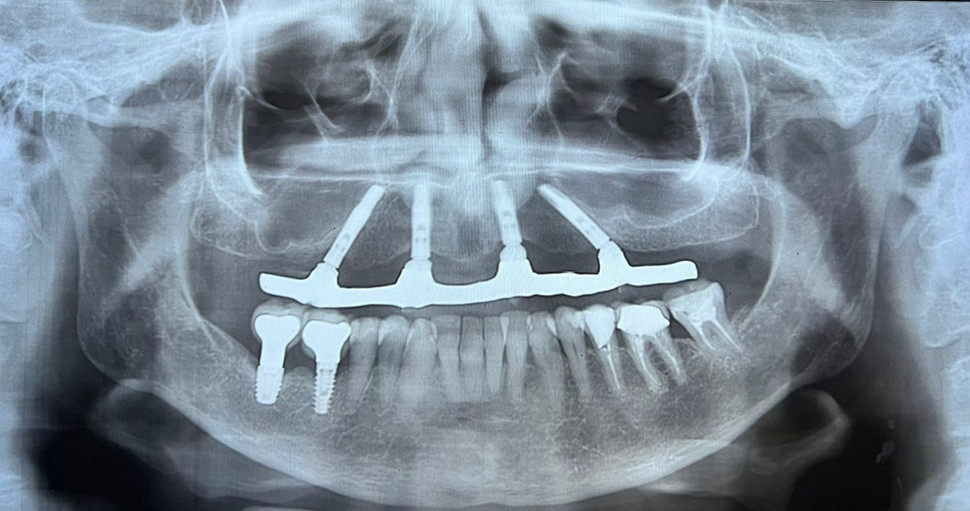

PRÓTESE TOTAL FIXA EM IMPLANTES

S.S.W.